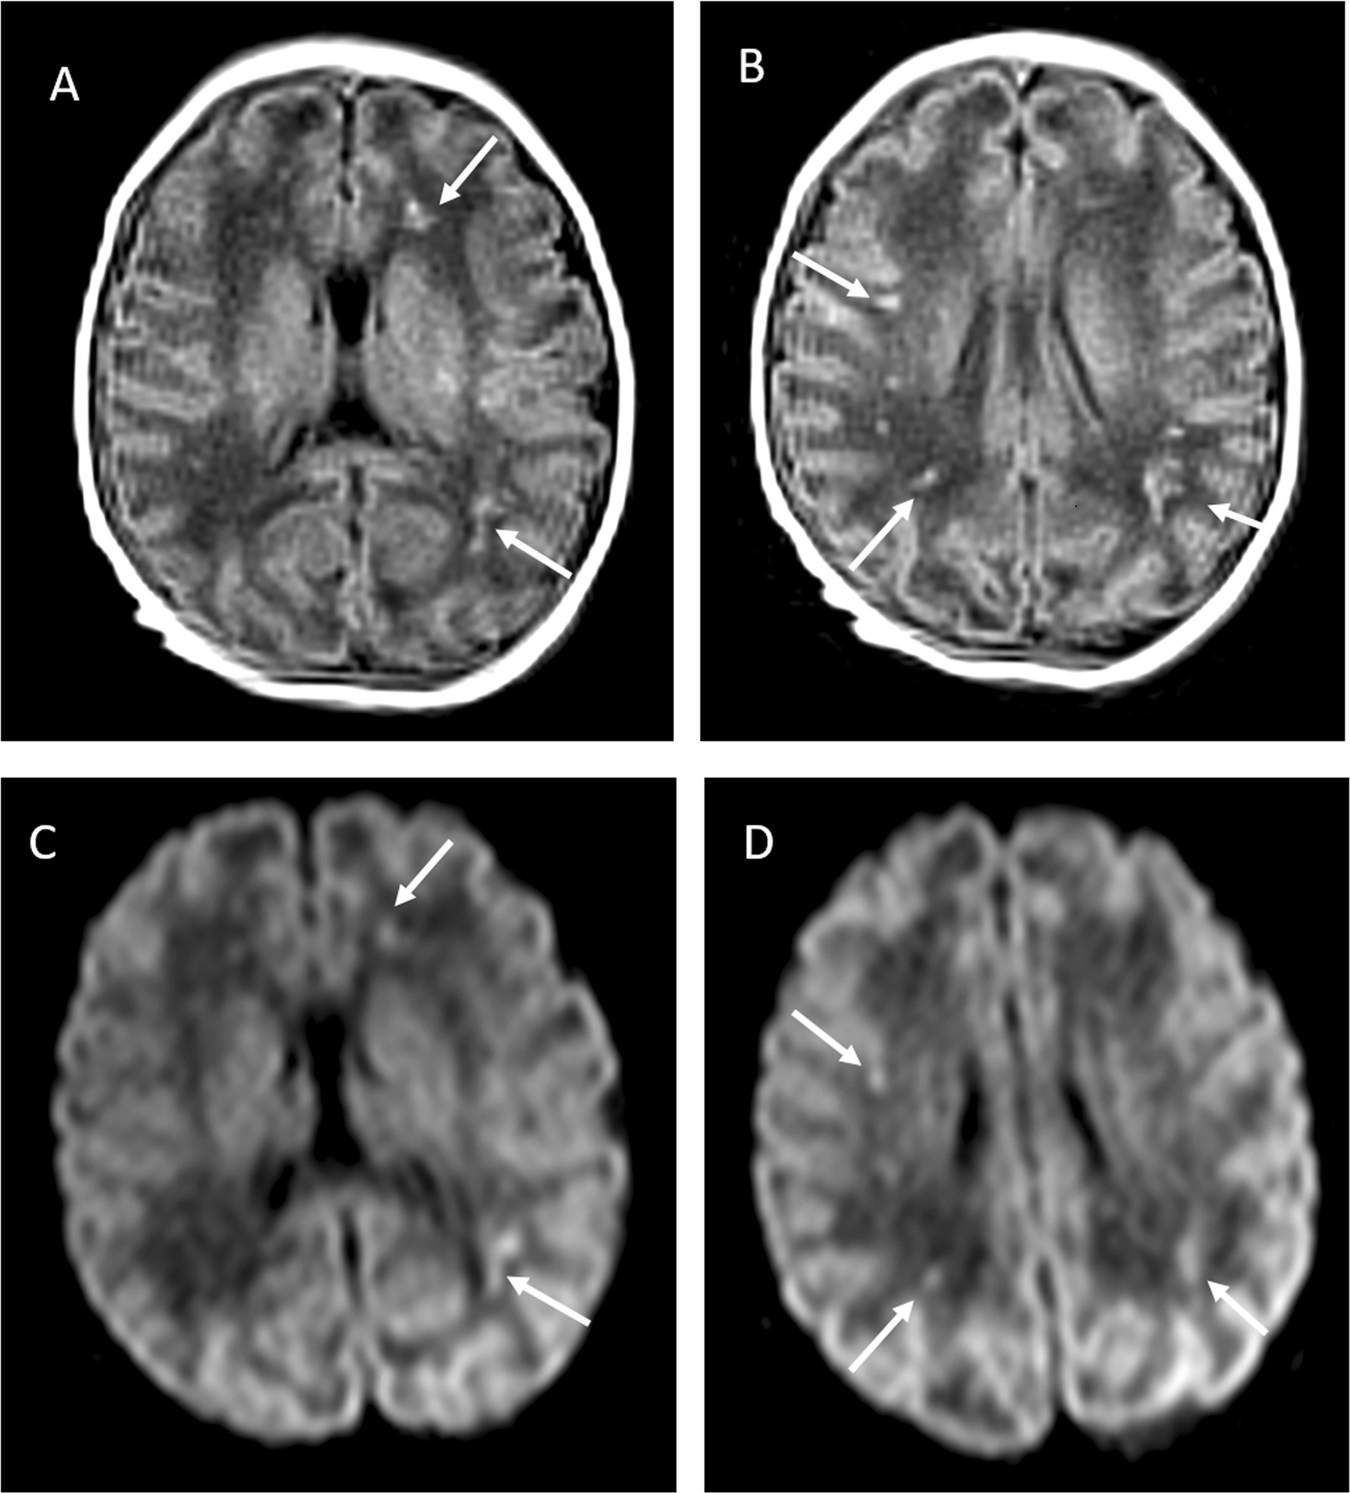

由于缺乏治疗新冠感染婴儿的临床指导,医生曾犹豫是否使用瑞德西韦,但男婴病症在3天内逐渐趋于好转,医生在男婴出生第5天采集的第二次脑脊液样本也显示正常,但是轻度张力减退和喂养困难仍然存在。医生在男婴出生后11天再次检测发现:男婴的核磁共振成像显示脑室周围白质和双侧额顶叶皮质下白质的高强度。

研究表明,根据男婴出生后近2个月的随访来看,男婴的神经系统检查和核磁共振成像显示进一步好转,生长及其他临床检查均显示正常。

“我们观察到一个真正在母体内感染新冠病毒的新生儿,而非‘污染’所致。”研究人员认为,“在此病例中,我们清楚地显示了该新生儿脑脊液中的神经系统症和炎症结果,由于新生儿没有受到其他病毒和病菌感染,神经影像学中表明的白质损伤可能是由新冠病毒感染引发的血管炎症引起,因为在成年患者中也发现了类似图像。”